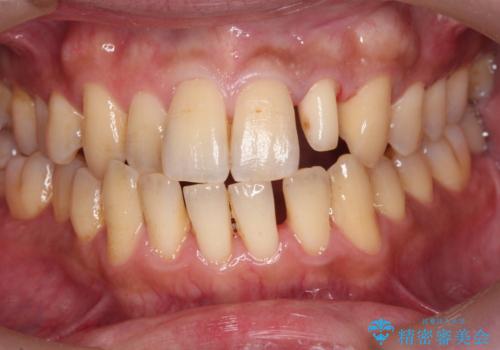

前歯のセラミック治療

- 左の前歯が黒いとのことで来院。

1番目の歯は小さい虫歯があったのでプラスチックの樹脂で治療をしました(保険内)。

2番目の歯は二箇所虫歯があり、プラスチックの樹脂で治療するとつぎはぎみたいになってしまうので、

白い被せ物(ジルコニアクラウン)で治療しました。

自然な被せ物が入り、大変満足して頂けました。